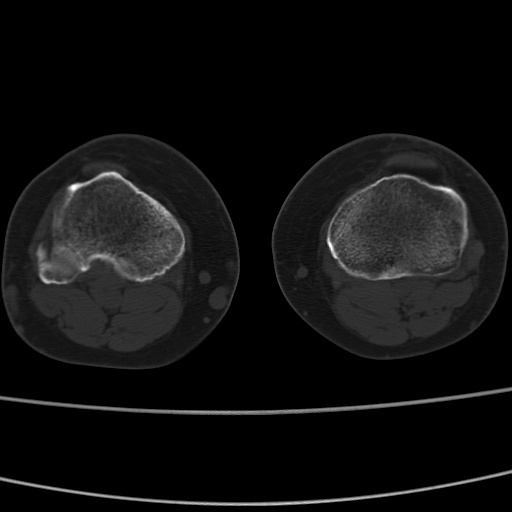

女性,50岁。【请提供患者临床症状体征】

右膝关节退行性改变,关节游离鼠。

右膝关节退行性改变,滑膜黏液囊钙/骨化并游离。